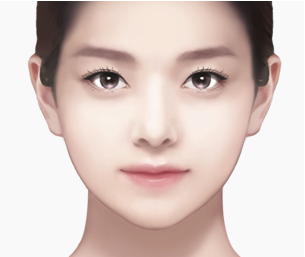

정밀한 분석과 적절한 양의 제거로

자연스럽고 세련된 결과를 완성합니다.

외부 흉터 Zero

입안을 절개하여

영구적인 효과

한 번 제거한 심부볼은

빠른 회복

비교적 간단한 수술로

자연스러운 라인

적절한 양만 제거하여

바이브성형외과는 과도하게 제거하지 않습니다.

얼굴 골격과 지방 분포를 정밀 분석하여

개개인에게 적합한 양만 제거함으로써

자연스럽고 균형잡힌 갸름한 얼굴을 완성합니다.